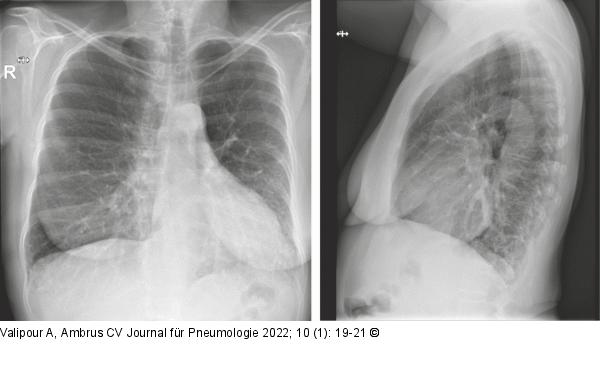

Abbildung 1: Thoraxröntgen

Thoraxröntgen p.a.